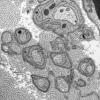

6A Axonal Degeneration (Case 29) EM 006 - Copy

6B1 (Case 6) EM 003 - Copy

6B2 (Case 6) EM 002 - Copy

6B2 (Case 6) EM 004 - Copy

6B3 (Case 6) EM 006 - Copy

6B4 (Case 6) EM 009 - Copy

6B4 (Case 6) EM 015 - Copy

6B5 (Case 6) EM 011 - Copy (2)